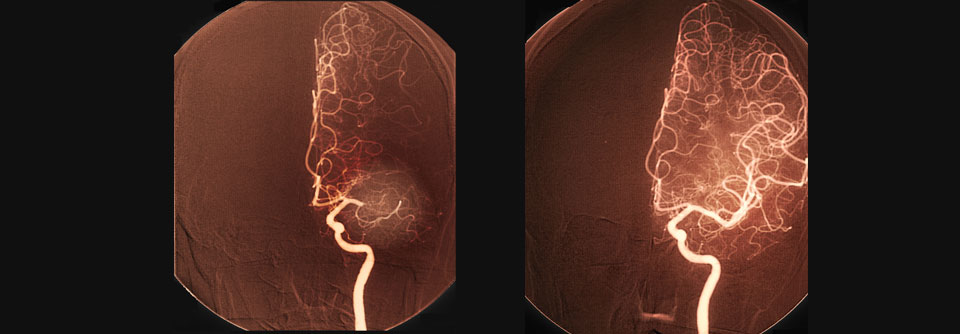

Hirnarterien einer 54-jährigen Patientin mit Mediainfarkt vor und nach der Thrombolyse.

Die Behandlung des ischämischen Schlaganfalls hat in den letzten Jahren einen bemerkenswerten Wandel durchlaufen. Moderne Thrombolytika, differenzierte Bildgebung und angepasste Leitlinien eröffnen neue Möglichkeiten – auch jenseits der klassischen 4,5-Stunden-Grenze.